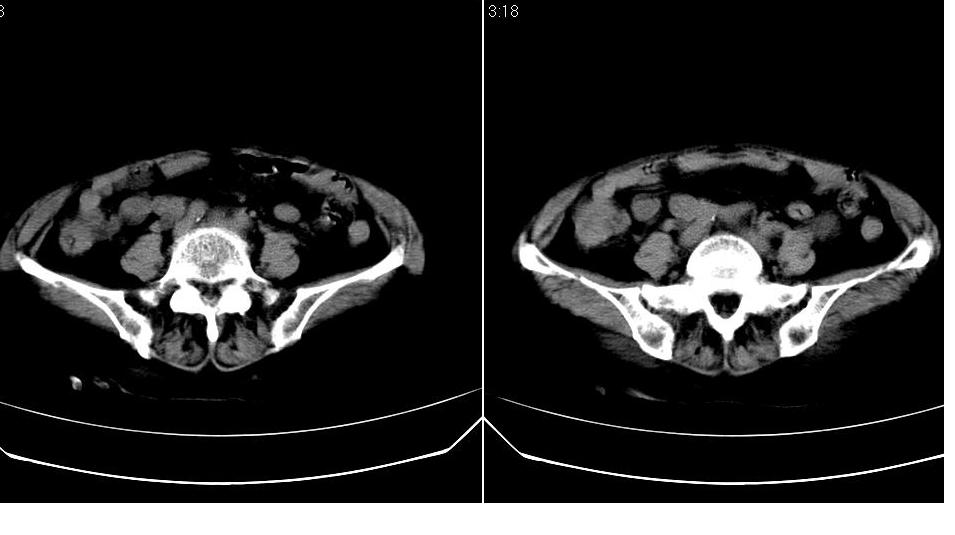

女,70岁,十天前在上级医院确诊宫颈癌,具体病史不详。

子宫形态增大,其内密度不均匀,宫颈部未见异常

子宫形态增大,其内密度不均匀,宫颈部未见异常,建议增强。

子宫体积增大,其内密度不均,考虑子宫内膜癌侵犯宫颈

宫颈癌阻塞性宫腔积液?累及宫腔?